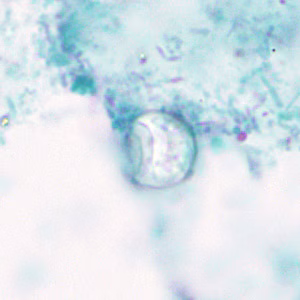

Cyclospora cayetanensis oocysts in wet mounts.

- Stained smears (using modified acid-fast stain or a modified safranin stain). Both modified acid-fast stains and modified safranin staining will stain Cyclospora cysts from a pink to brilliant red. Staining may be more variable using modified acid-fast.